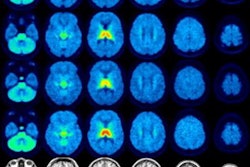

Right and left hemisphere brain surface plots showing the strength of the canonical vector, for each subtype. Image and caption courtesy of Joyita Dutta, PhD, and the SNMMI.Right and left hemisphere brain surface plots showing the strength of the canonical vector, for each subtype. Image and caption courtesy of Joyita Dutta, PhD, and the SNMMI.

The four Alzheimer's disease subtypes can be identified by a computational method that incorporates genomic and tau PET imaging data, according to a study presented at the annual Society of Nuclear Medicine and Molecular Imaging (SNMMI) meeting.

The method identified medial temporal lobe (MTL)-dominant, posterior, MTL-sparing, and lateral-temporal subtypes of Alzheimer's disease. It also identified the top genes associated with each subtype, in addition to the apolipoprotein E gene (APOE) gene.